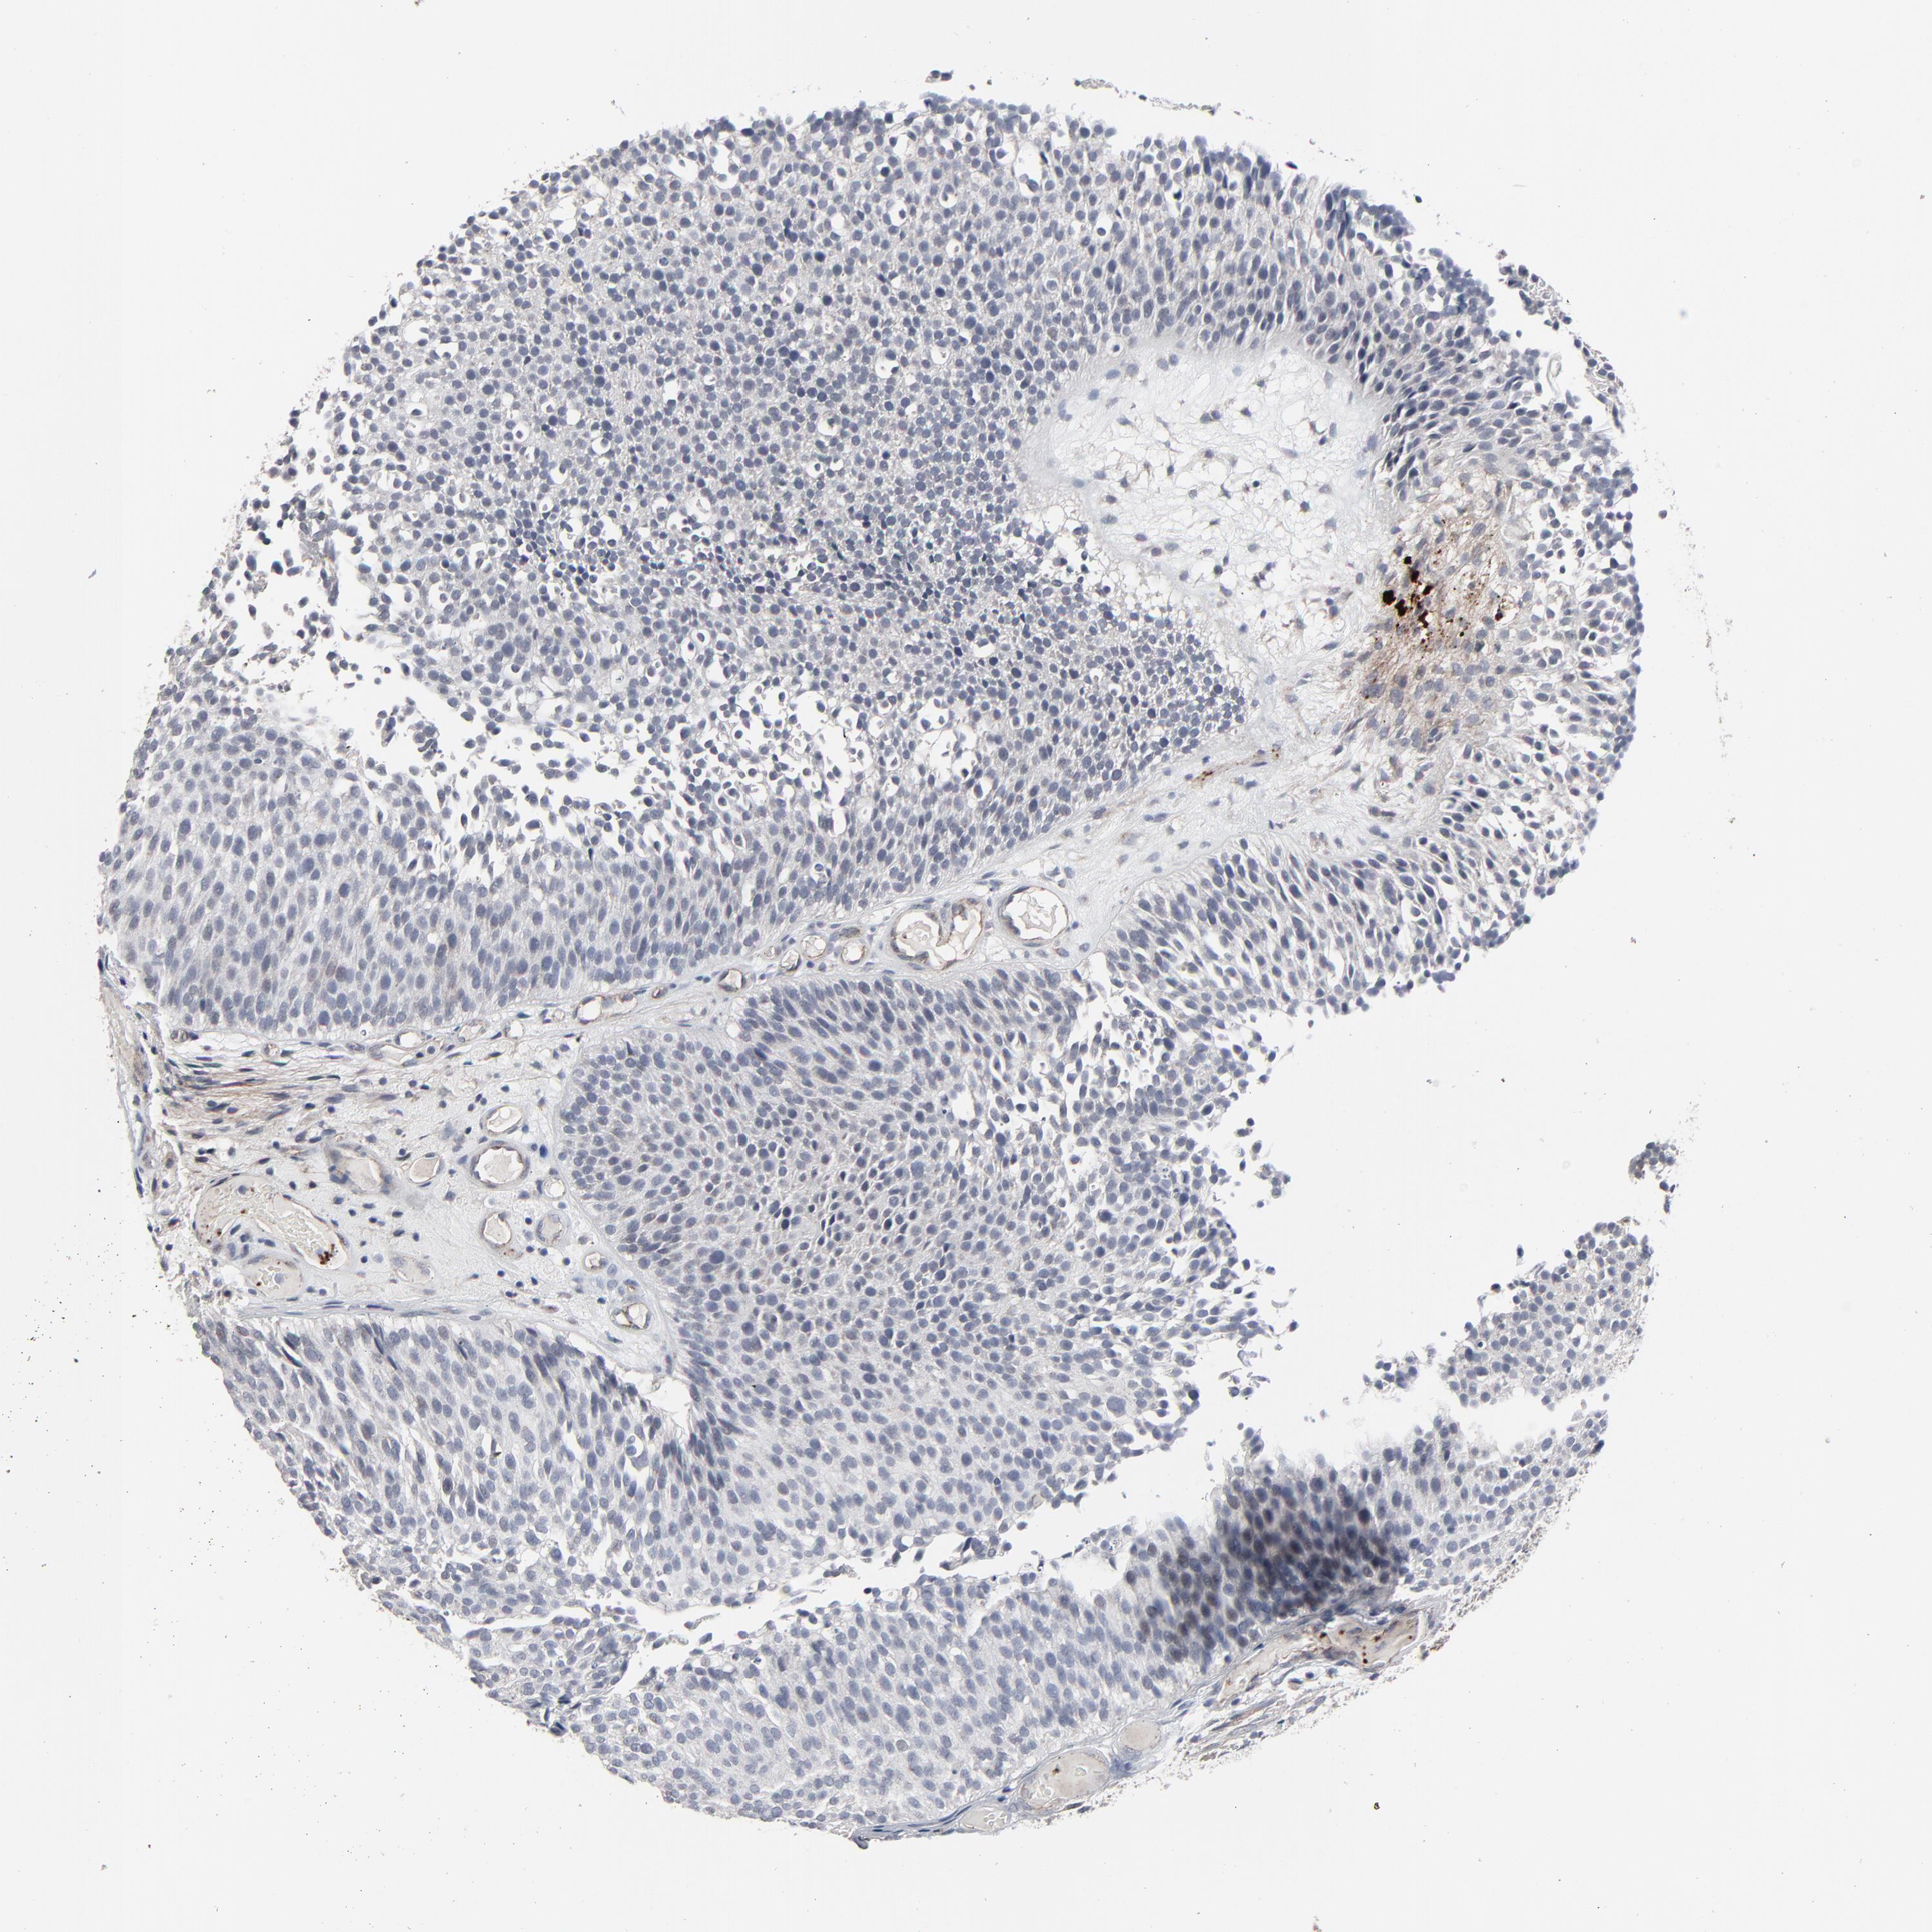

UROTHELIAL CANCER - Protein expressioni

A mouse-over function shows sample information and annotation data. Click on an image to view it in a full screen mode. Samples can be filtered based on level of antibody staining by selecting one or several of the following categories: high, medium, low and not detected. The assay and annotation is described here.

Antibody stainingi

Antibody staining in the annotated cell types in the current human tissue is reported as not detected, low, medium, or high, based on conventional immunohistochemistry profiling in selected tissues. This score is based on the combination of the staining intensity and fraction of stained cells.

Each image is clickable and will lead to virtual microscopy that enables deeper exploration of all samples and also displays staining intensity scores, fraction scores and subcellular localization as well as patient and tissue information for each sample.

Antibody HPA003417

Staining

High

Medium

Low

Not detected

Intensity

Strong

Moderate

Weak

Negative

Quantity

>75%

75%-25%

<25%

None

Location

Nuclear

Cytoplasmic/membranous

Cytoplasmic/membranous,nuclear

Urothelial carcinoma, High grade

Urothelial carcinoma, Low grade